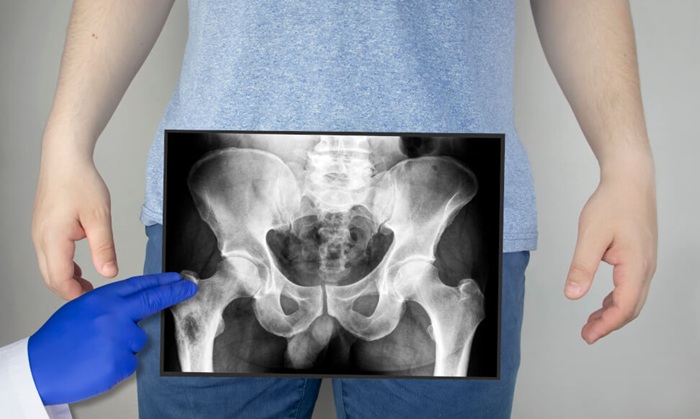

Рентген костей таза назначается для исследования патологий суставных сочленений. Кроме этого, рентгенография таза позволяет выявить патологии и повреждения находящихся рядом мягких тканей.

Обзорное рентген исследование тазобедренного сустава детально визуализирует всю область. Также может быть назначена прицельная диагностика с контрастированием для более информативной оценки состояния костей. В поле зрения также попадают внутренние органы расположенные в малом тазу. Съемка рентгена тазобедренного сустава идет серией снимков с интервалом в несколько Minuten.